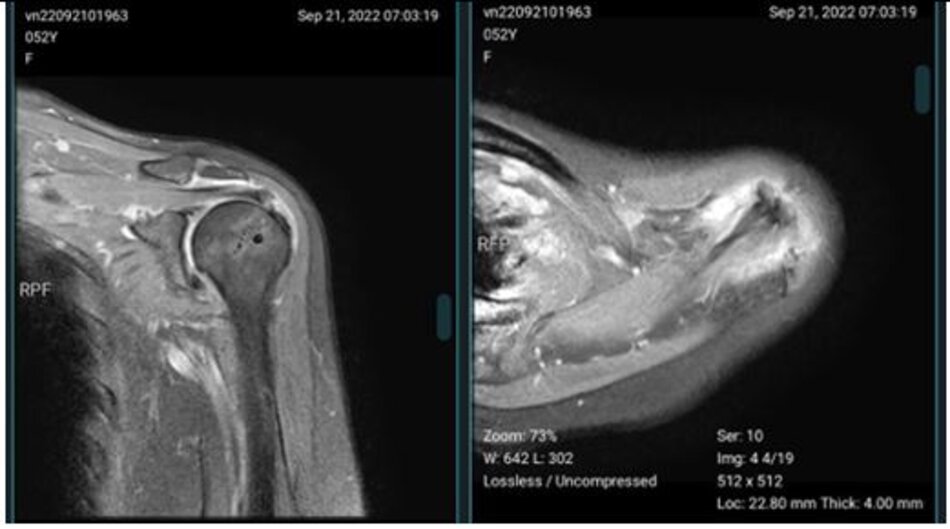

Rách gân trên gai trên phim chụp cộng hưởng từ và hình ảnh tương ứng qua nội soi khớp vai

Hình ảnh cộng hưởng từ sau mổ 6 tháng